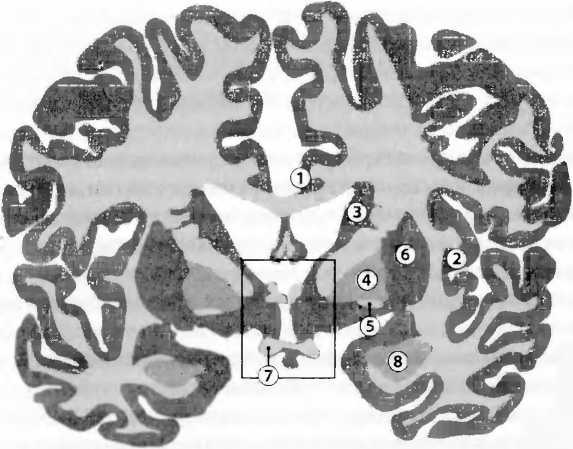

Рис. 26. 1) Цингулярная (поясная) кора, область треноги; 2) инсулярная (островковая) кора, активная при эмоциональных переживаниях, координирует телесные, автономные реакции; 3) nucleus caudatus (хвостатое ядро), моторика и эмоции; 4) globus palliclus (бледный шар), моторика; 5) ventral pallidum/nucleus accumbens (вентральные отделы бледного шара/прилежащее ядро), вознаграждение; 6) putamen (скорлупа), моторика; 7) оптическая хиазма, пересечение ’зрительных не рвов: 8) миндалевидное тело, страх, агрессия и сексуальное поведение. Гипоталамус заключен в рамку.

У японских монахов, как показала функциональная томография, различные виды медитаций стимулировали различные области мозга. Речь идет о частях префронтальной коры (рис. 14) и латеральной, теменной коре (рис. 1). Кроме того, религиозные убеждения сочетаются с меньшей активностью передней части циркулярной (поясной) коры (АСС, anterior cingulate cortex, рис. 26), что отмечается также и для политического консерватизма. Хотя причины этих соотношений неясны, интересно, что проявление инициативы сочетается с повышенной активностью в АСС. На электроэнцефалограмме (ЭЭГ) монахинь-кармелиток отмечались сильные изменения во время мистических переживаний. Мистическое переживание заключается в чувстве единения с Богом. При этом человек верит, что обрел последнюю истину, у него исчезает ощущение пространства и времени, он чувствует единство с человечеством и вселенной, его охватывает чувство мира, радости и бесконечной любви. Нейрофармакологические исследования указывают на то, какое большое значение для этих переживаний имеет активация дофаминовой системы вознаграждения (рис. 15). Болезни мозга также дают здесь существенную информацию. Так, болезнь Альцгеймера связана с возрастающей утратой религиозного интереса. Чем медленней развивается эта болезнь, тем меньше она затрагивает степень религиозности и спиритуальности. Гиперрелигиозность, напротив, обнаруживается при лобно-височной деменции, мании, обсессивно-компульсивных расстройствах (навязчивых состояниях), шизофрении и височной эпилепсии. О некоторых из этих болезней известно, что они сопровождаются повышенной активностью дофаминовой системы вознаграждения.

При проведении функциональной томографии монахинь-кармелиток просили вспоминать о своих мистических переживаниях. Когда монахини заново воссоздавали их в своем воображении, возникала сложная картина активности различных областей мозга: (i) активация средней части височной доли, что может быть связано с чувством единения с Богом, — эта область активируется также при височной эпилепсии, при которой могут возникать сильные религиозные переживания (рис. 27); (in активация хвостатого ядра (nucleus caudatus, рис. 26), области, где обрабатываются эмоции, что может быть связано с переживанием чувства радости и бесконечной любви; (iii) активация стволовой части мозга (рис. 20), инсулярной (островковой) области мозга (рис. 26) и префронтальной коры (рис. 14), что может быть связано с автономными телесными реакциями, сопровождающими эти эмоции и их осознание в коре. При этом происходила (iv) активация латеральной теменной коры, что может быть связано с чувством изменений в телесной схеме, близким околосмертному состоянию (рис. 27).